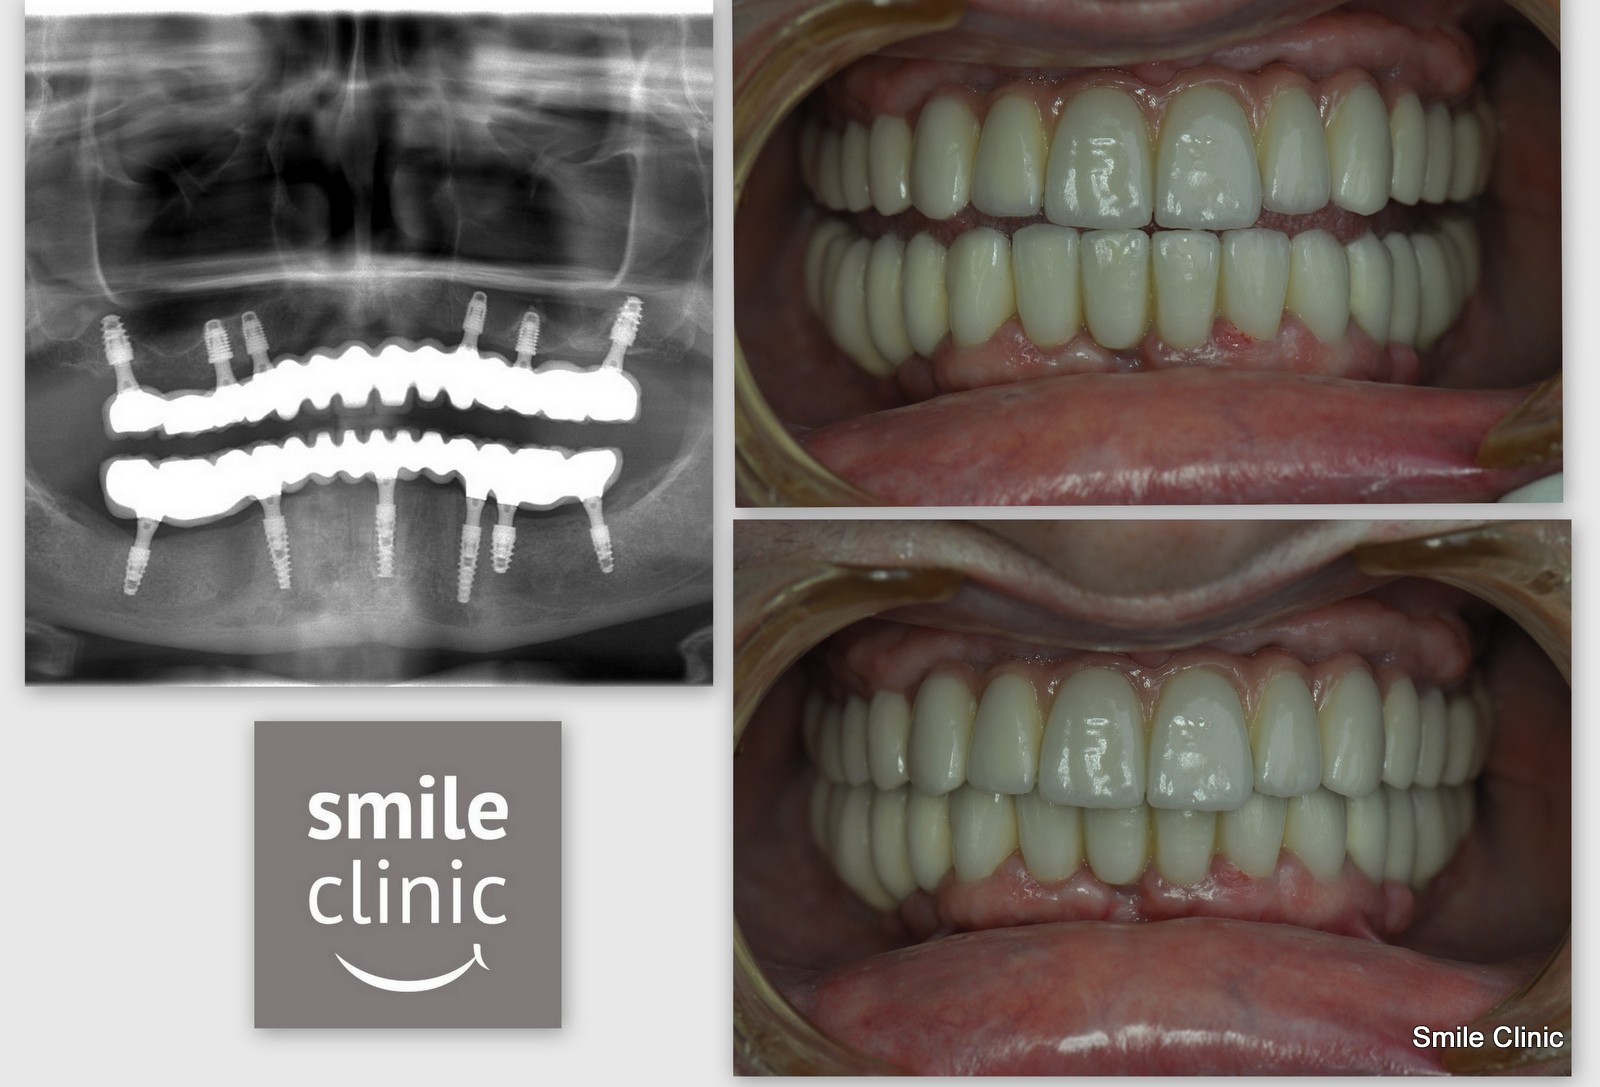

As you can see from the X-ray, 6 dental implants were placed to both the upper and lower jaws supporting 12 teeth. The result was amazing, and you hear exactly what a difference it has had for Aileen in her testimonial.

After wearing two plates and having missing teeth for many years I cannot speak highly enough about the clinic and its staff. There were so many little things that made a great difference for me. The car from the airport, telephone calls, emails, English speaking staff, nothing was too much trouble.

I have a very beautiful set of teeth now and a very confident smile. Piestany is also a beautiful place to explore and take spa treatments. I have absolutely no hesitation about recommending this clinic and its staff.